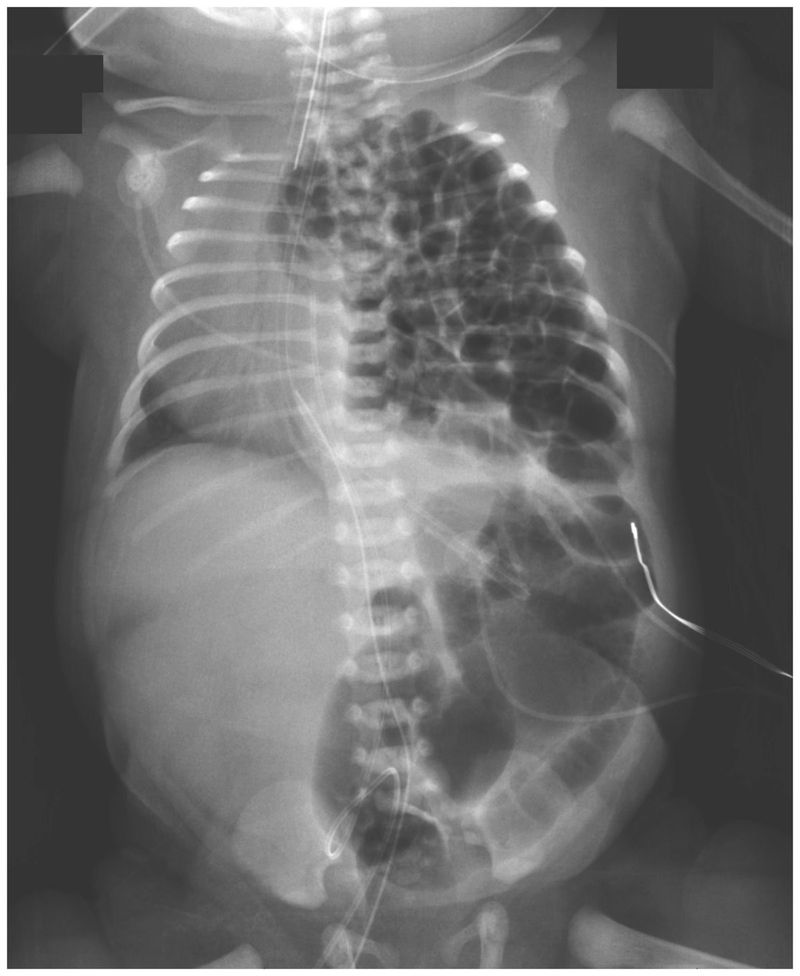

A female infant was delivered by planned cesarean section at 36 weeks of gestation because of a prenatal diagnosis of congenital diaphragmatic hernia. The neonate was intubated immediately after delivery. A nasogastric tube was inserted and suction begun to decompress the bowels to allow for better lung expansion. Chest radiography revealed multiple loops of bowel occupying the left hemithorax, which shifted the cardiothymic structures to the right. Congenital diaphragmatic hernia occurs when the diaphragm muscle fails to close during fetal development; the defect can occur on the right side, left side, or, on rare occasions, both sides. Defects on the right side, which manifest with the liver in the chest, are treated with diaphragmatic patch repair and are associated with higher rates of high-frequency ventilation, extracorporeal membrane oxygenation, and death than are defects on the left side. In our patient, the posterolateral diaphragmatic defect, also called a Bochdalek hernia, measured 3 cm by 4 cm, and because of the more favorable location on the left side, the defect was fixed surgically by primary repair on the third day of life. After the surgery, the patient received high-frequency ventilation but not extracorporeal membrane oxygenation. She was discharged home from the neonatal intensive care unit after 1 month and did well. However, the defect recurred 6 months later, and a second operation was performed. Jared Klein, M.D. Megan Sirota, M.D. Children’s Hospital of Richmond at Virginia Commonwealth University, Richmond, VA source:nejm.org